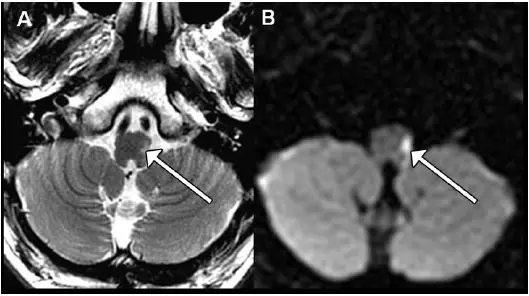

图 1.

2.后循环动脉系统包括颈部椎动脉、颅内椎动脉、基底动脉、大脑后动脉等及其分支(图 1);

3.闭塞部位不同,引起的临床表现不同(图 1、图 2);